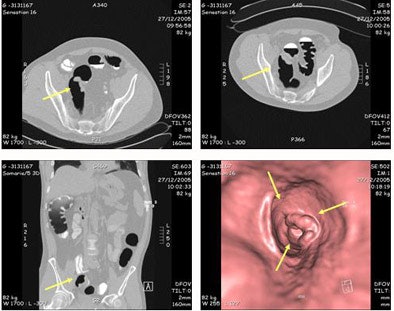

![]() |

| A sigmoid tumor, 5 x 2 cm in size, was detected at both VC and colonoscopy. The lesion was a well- to moderately differentiated transmural invasive adenocarcinoma classified as pT3N2Mx R0. Images courtesy of Dr. Didier Bielen. |

For lesions 8 mm and larger, VC's specificity and sensitivity (positive and negative predictive values) were 91% and 99%, respectively, Bielen said, and 100% for lesions 10 mm and larger.